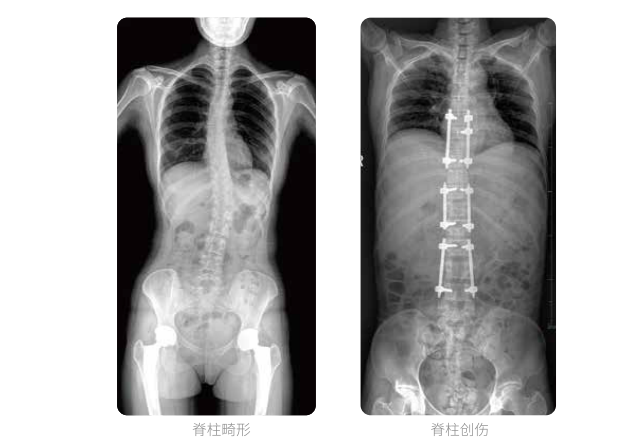

近年来,脊柱及下肢畸形的患者较多,多发于青少年的脊柱侧弯畸形,骨性关节炎、风湿性关节炎以及双下肢畸形如膝关节内外翻、X型O型腿等也是骨科常见病。并且发病率呈现逐年升高的趋势,常常累及下肢髋、膝、踝3个负重关节,影响患者生活,甚至丧失工作能力。

在脊柱及下肢畸形的临床治疗过程中,一般需要进行矫正手术治疗,在对其进行手术前后,均需要拍摄X光片以便分析病情、明确诊断和观察治疗效果。常规DR拍摄面积有限,最大规格仅有43cm,但成人男性全脊柱长度平均为70-75cm,女性为66-70cm,而双下肢更长。华体会体育登入首页PLX8600动态DR的43cm*86cm超大有效视野,可一次性拍摄全脊柱、双下肢的影像视野。

常规DR摄片技术不能一次性拍摄出完整的全脊柱或双下肢的X光影像。全脊柱的拍摄需要分别拍摄颈椎、胸椎、腰椎的X光片,虽然能够观察到局部的侧弯情况,但不能观察到三者之间的连续性,这就增加了这类疾病的诊治难度。

华体会体育登入首页动态数字化X线摄影(动态DR)拥有43cm*86cm超大有效视野,使全脊柱及双下肢能够得到完整清晰的成像,为临床在脊柱侧弯畸形和下肢骨关节病变诊断、治疗方案制定及治疗后复查提供精准的测量。

全脊柱临床影像

华体会体育登入首页动态数字化X线摄影(动态DR)可以使整个脊柱一次成像,直观显示脊柱的整体形态以及侧弯部位,评价侧弯的病理程度,全面了解脊柱各个阶段的生理曲度及椎间关节连接的关系,避免了常规脊柱摄影对整个脊柱曲度的影响。为脊柱侧弯的诊断治疗提供了重要的影像学依据。